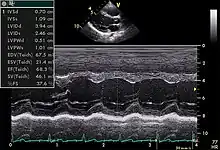

TTE utilizes one- ("M mode"), two-, and three-dimensional ultrasound (time is implicit and not included) from the different windows. These can be combined with pulse wave or continuous wave Doppler to visualize the velocity of blood flow and structure movements. Images can be enhanced with "contrast" that are typically some sort of micro bubble suspension that reflect the ultrasound waves.

Motion mode is infrequently used in modern echocardiography. It has specific uses and has the benefit of very high temporal fidelity (e.g., measuring LV size at end diastole).